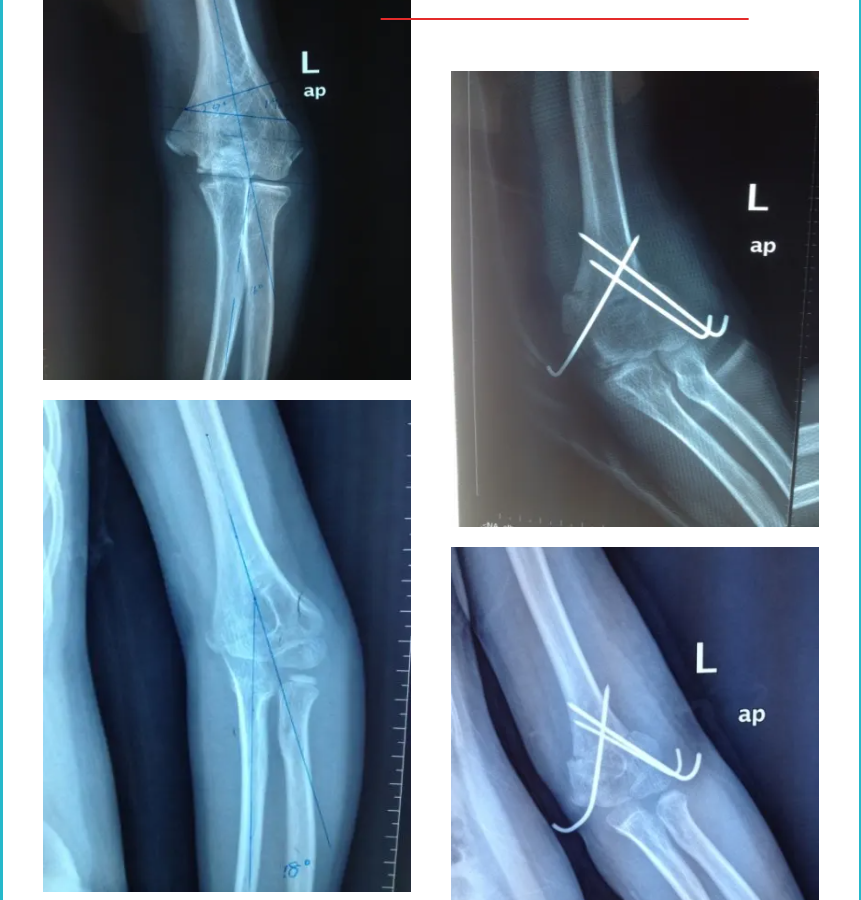

肘部畸形

肘內(nèi)翻矯正